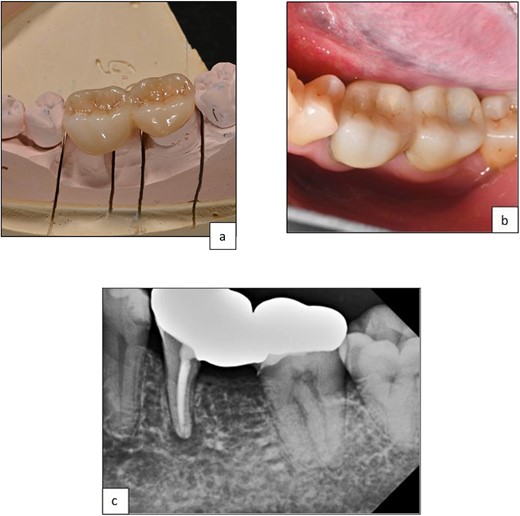

The patient was monitored for one year with no reported symptoms. Due to extensive filling and secondary caries in the adjacent left second mandibular molar (tooth 37), both the mesial root of tooth 36 and tooth 37 were prepared for a zirconia bridge. Tooth 36 received a full-coverage crown, while tooth 37 was restored with an onlay. Tooth 36 was anatomically restored to conform esthetically and functionally with the existing occlusion (Fig. 4 and 5).

Clinical photographs showing (a) zirconia bridge design, (b) final prosthesis after cementation, (c) periapical radiograph post-cementation of zirconia, the bridge shows a good adaptation of the restorative margins.